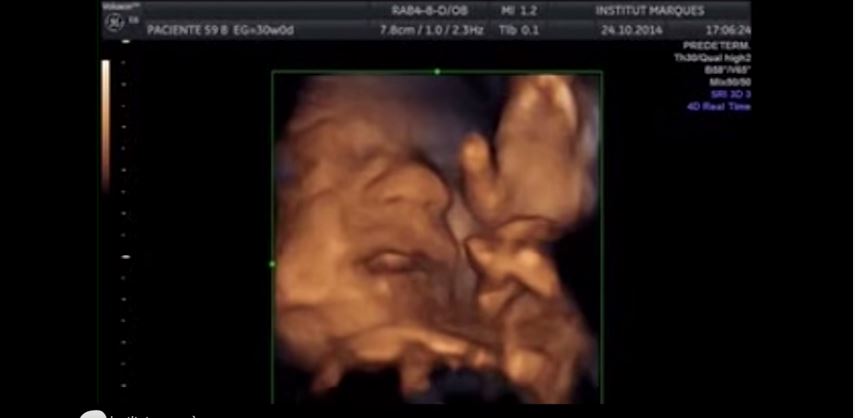

Publiée dans le journal britannique Ultrasound de la British Medical Ultrasound Society, une étude principalement menée par la chercheuse Dr Marisa Lopez-Teijon a montré que votre bébé était très réceptif à la musique. En effet, à partir de la seizième semaine de grossesse, l’oreille du fœtus est formée et répondrait aux sons, et plus particulièrement à « La Partira en La mineur pour flûte traversière » de Jean-Sébastien Bach. Comme on peut le voir sur la vidéo montrant une échographie, le bébé bouge sa bouche mais aussi sa langue en entendant le son qui a été diffusé contre le ventre de la maman, et de manière intravaginale en mettant un haut parleur spécial à l’intérieur du vagin. Selon la spécialiste espagnole, la musique stimulerait la partie du cerveau qui contrôle la communication.

L’étude a alors démontré que 45% des fœtus ont bougé la tête et leurs parties du corps, 30% ont bougé la bouche et la langue et 10% ont carrément tiré la langue ! L’étude se conclut ainsi : « Nous connaissions l’importance de parler aux bébés dès la naissance, afin de favoriser la stimulation neurologique. Maintenant, nous avons l’incroyable occasion de commencer cette stimulation beaucoup plus tôt : c’est une énorme avancée »… Du Bach à fond pour bébé maintenant !